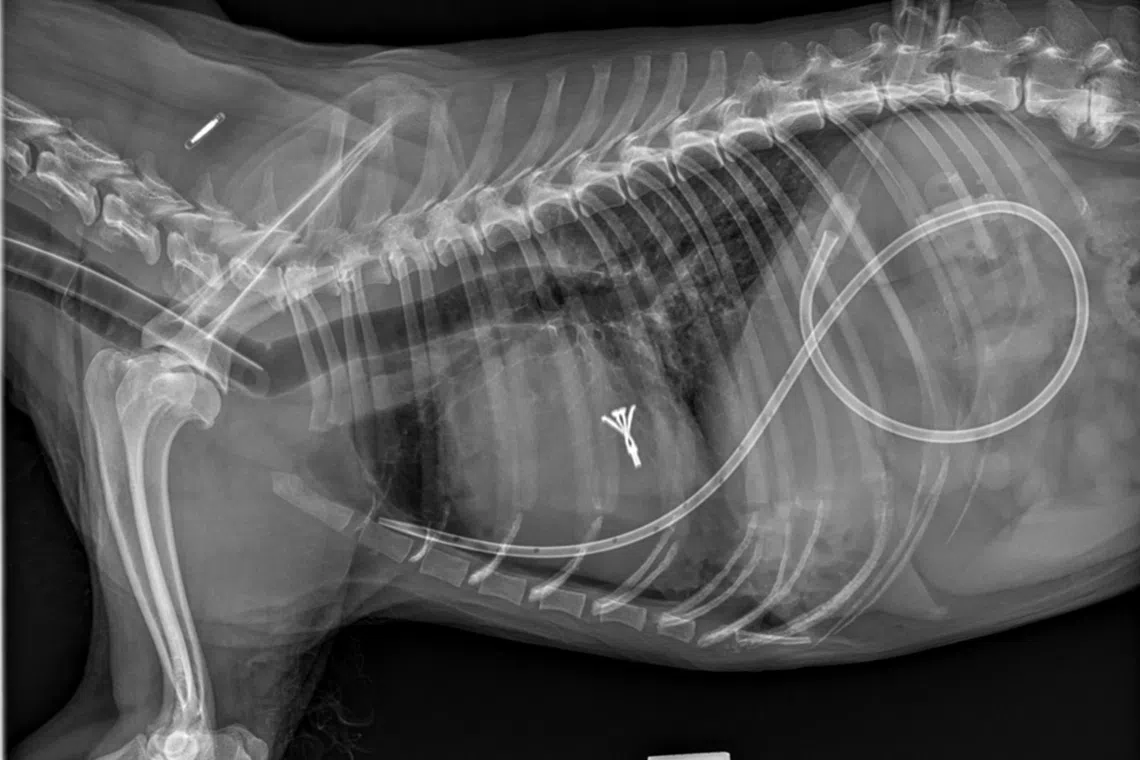

Two hours after Dingding’s surgery, her heart is smaller, after a clip was put in place to repair the valve prolapse. There is a temporary chest tube placed for monitoring purposes.

PHOTO: ATLAS VET